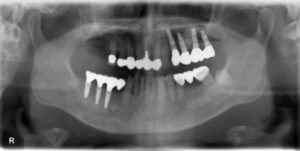

上顎大臼歯2本欠損症例

BEFORE AFTER 66歳男性/上顎2本欠損/インプラント埋込手術 【治療内容】 右上臼歯の欠損補綴のご相談でご来…